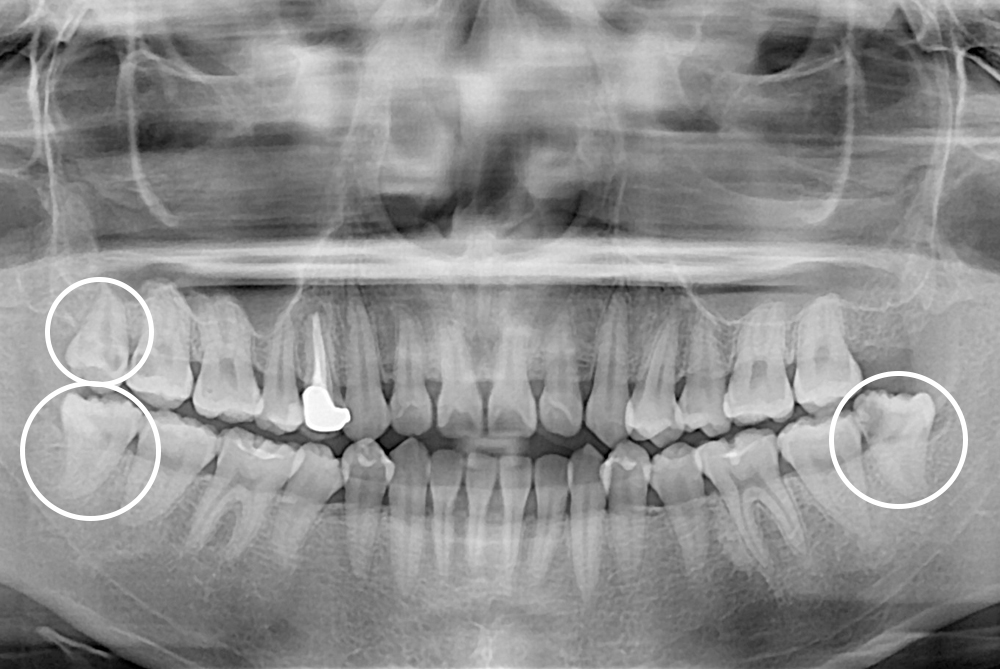

[사랑니] 매복 사랑니 발치

치료후 : 2021-05-31

세종치과는 구강악안면외과학 박사이신 원장님이 발치하는 치과입니다.